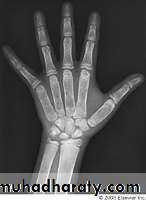

Radiographic features:

Clavicuiar lysis, Subperiosteal resorption

Brown tumors ,General osteopenia

(Bone resorption is virtually pathognomonic(Subperiosteal resorption

Radial aspect of middle phalanges

(especially index and middle finger)

Phalangeal tufts

Trabecular resorption

Tunneling of MCP bones (nonspecific)